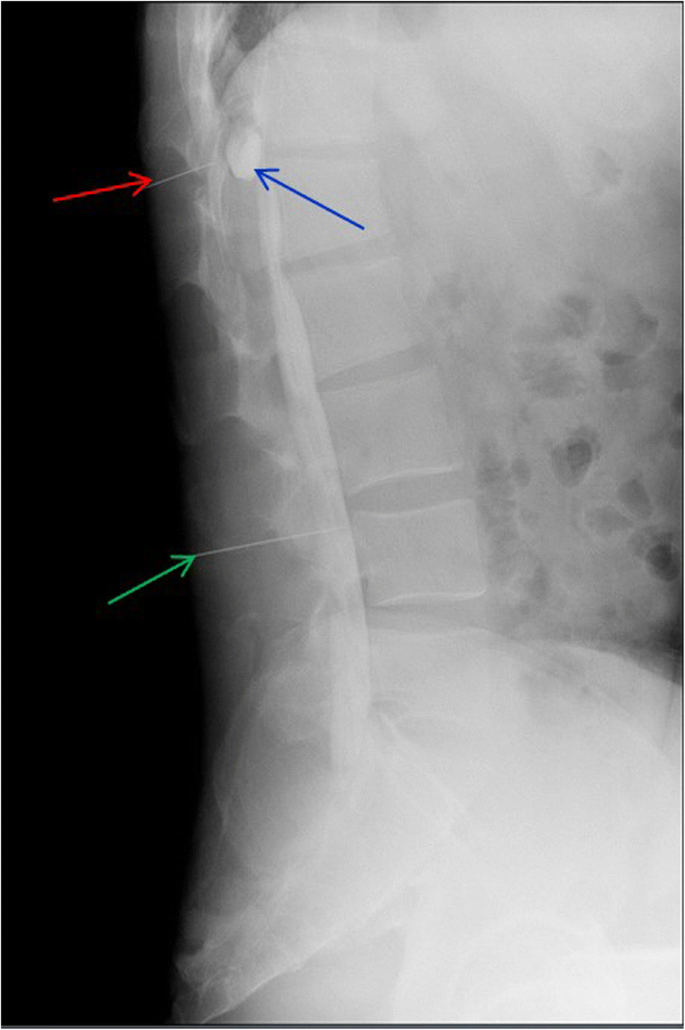

This is a 26-year-old man who experienced right lower limb weakness for 2 years and the weakness exacerbated in last half year. He visited the second affiliate hospital of the Zhejiang University School of Medicine. A physical examination indicated the result of the straight leg raising test was positive and also muscle atrophy. The muscle power of the right lower limb had decreased to grade 3. There was no sensory impairment. Magnetic resonance imaging revealed an intraspinal extradural tumor over T10 to L3 (Fig. 1). It appeared to be a spinal extradural arachnoid cyst (SEAC). To confirm whether the fistula existed between the subarachnoid space and arachnoid cyst, and to localize the position of the fistula, we performed a real-time technique. First, we injected contrast medium into the cyst under fluoroscopy. After 1 h the follow-up computed tomography (CT) was administered, and it revealed there was no contrast-infiltration into the subarachnoid space (Fig. 2). We then extracted about 20 mL of fluid from the cyst. The follow-up magnetic resonance imaging on the same day indicated the cyst did not become smaller (Fig. 3). A “one-way valve” fistula was suspected such that cerebral spinal fluid could pass into the cystic space from the subarachnoid space but could not flow in the opposite manner. Therefore we designed a procedure to localize the fistula. We penetrated two needles into the cyst and subarachnoid space separately in the L3/L4 level under digital subtraction angiography (Fig. 4). Pending the fluid drained through those two needles, we injected 10 mL of contrast medium slowly into the subarachnoid space and a little contrast medium infiltrated into the cystic space horizontally at the T12/L1 level. We then administered high resolution computed tomography (HRCT) immediately to confirm the position in the axial plane. The HRCT revealed a funnel-shaped enhancement between the lower edges of the T12 body and the left nerve root, and this is the accurate position of the fistula (Fig. 5).

Utilizing two needles, punctured into the cystic space (red arrow) and subarachnoid space (green arrow) under digital subtraction angiography (DSA), drains the fluids. In this way, pressure is balanced between the two spaces. The 10 mL of contrast medium was then injected into the subarachnoid space (from the lower needle). Under DSA, we observed contrast medium infiltrating into the cystic space at the T12/L1 level (blue arrow)